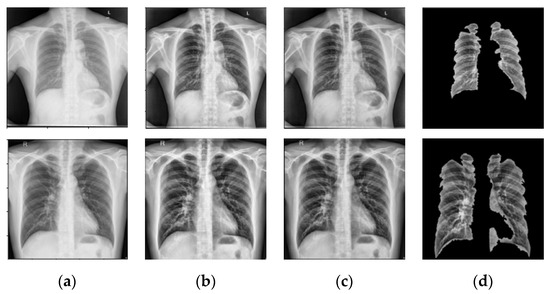

- NLM (National Library of Medicine) dataset [16,20,21]: This was made by two publicly accessible datasets including the Montgomery County CXR set (MC) and Shenzhen (CHN) dataset. The MC dataset was compiled in collaboration with Montgomery County, Maryland, the United States’ Department of Health and Human Services. The collection includes 138 frontal CXRs from Montgomery County’s tuberculosis screening program, where 80 CXRs were normal cases while 58 CXRs had TB manifestations. The X-rays were taken with a Eureka stationary X-ray machine (CR) and provided as 12-bit gray level images in portable network graphics (PNG) format. Moreover, the Digital Imaging and Communications in Medicine (DICOM) format is also available upon request. The X-rays were either 4020 × 4892 or 4892 × 4020 pixels in size. The Shenzhen dataset was collected in collaboration with Shenzhen No. 3 People’s Hospital, Guangdong Medical College, Shenzhen, China. The CXRs were from outpatient clinics and captured as part of the daily hospital routine within a 1-month period, mostly in September 2012, using a Philips DR Digital Diagnost system. The dataset contained 662 frontal CXRs, of which 326 belonged to normal cases while 336 had TB manifestations including pediatric X-rays (AP). The X-rays are provided in PNG format, and can vary in size, but is approximately 3 K × 3 K pixels.

- Belarus dataset [20]: The National Institute of Allergy and Infectious Diseases, Ministry of Health, Republic of Belarus, collected the Belarus Set for a drug resistance study. There are 306 CXRs in the dataset, representing 169 patients. The Kodak Point-of-Care 260 system was used to take chest radiographs with a resolution of 2248 × 2248 pixels. All images in this database had been infected with tuberculosis.

- RSNA dataset [20]: The RSNA pneumonia detection challenge dataset contains approximately 30,000 chest X-ray images, 10,000 of which were normal and the rest were abnormal as well as the lung opacity images. The DICOM format was used for all images. A total of 3094 normal images were taken from this database and the remaining 406 normal images were taken from the NLM database to create a normal database of 3500 chest X-ray images for this study.

6.1. Weiner Filtering

6.2. Prior TB Segmentation

6.4. Prewitt Edge Detection